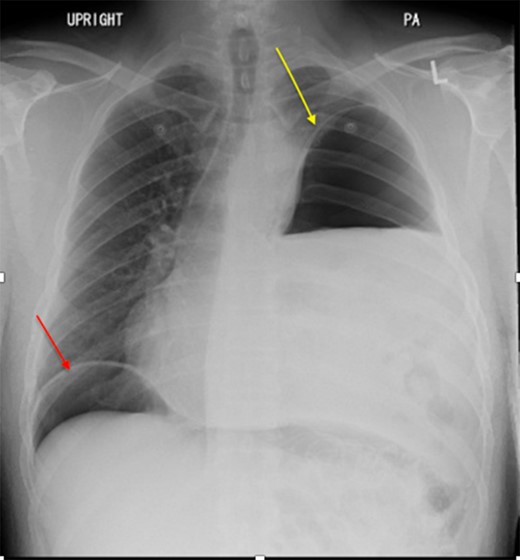

We present a 44-year-old male patient came to the emergency department complaining of right upper quadrant abdominal pain. The patient reported taking over-the-counter (OTC) ibuprofen intermittently for a past few months due to backaches. His past medical history is only positive for falling off a 15 feet ladder at the age of 15 years old. Upon examination, he had right upper quadrant abdominal tenderness, a heart rate of 90 beats/min and a respiratory rate of 20 breaths/min on room air. The patient clinical status was stable and looked well. Chest x-ray showed a moderate left hemidiaphragm elevation with bowel contents overlying the left chest (Fig. 1). Of note, a large amount of air inferior to the right hemidiaphragm was indicative for pneumoperitoneum. Laboratory investigations were immediately carried out and revealed a white blood cell count (WBC) of 4.5 × 109/L (normal range: 4–11 × 109/L). The WBC remained at the normal level until the end of the patient’s admission. Further imaging studies were ordered due to the peculiar coexistence of x-ray findings and stable clinical status. The computed tomography (CT) scan showed a contracted left lung with severe volume loss and just mild aeration of the left upper lung (Fig. 2). No definite left pneumothorax was seen. The majority of the left hemithorax was filled with abdominal contents including the stomach, spleen, pancreatic tail, left kidney, splenic flexure of the colon, and small bowel loops. A small hypodense focus was observed within the intra-thoracic stomach and extended to the stomach wall, with mild adjacent stranding of fat and a small amount of free fluid. We suspected the presence of perforated gastric ulcer secondary to non-steroidal anti-inflammatory drugs (NSAIDs) usage. The upper gastrointestinal (GI) series was performed and did not show any extravasation, indicating that there was some other source or the gastric perforation had walled off. The patient was thus managed conservatively; his diet was advanced and the patient discharged home on Day 4.

Chest x-ray showed a moderate left hemidiaphragm elevation with bowel contents overlying the left chest.